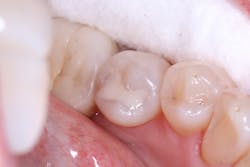

The first case demonstrates a molar with the often-typical A1/B1 shade. It required an occlusal restoration. Following local anesthesia, a DryShield isolation device was placed intraorally. The cavity was accessed and cleaned (figure 1). After rinsing and gentle drying of the dentin, Tokuyama Universal Bond (Tokuyama Dental America), an eighth-generation bonding agent, was applied and dried, without the need for light curing. The Omnichroma composite was built up and cured in 2 mm increments until the tooth was fully restored (figure 2). Note that prior to curing, Omnichroma will appear opaque white. Then, following curing, it immediately blends into the surrounding tooth structure. The occlusion was adjusted, and the composite and surrounding enamel was polished.